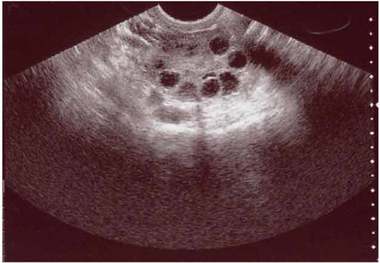

• فیبروم چیست؟ + راه های درمان

فیبروم چیست؟ + راه های درمان

متخصص زنان و زایمان گفت: تشکیل فیبروم ممکن است در دوران بارداری باشد که البته این مسئله با تشخیص و اقدام به موقع به…